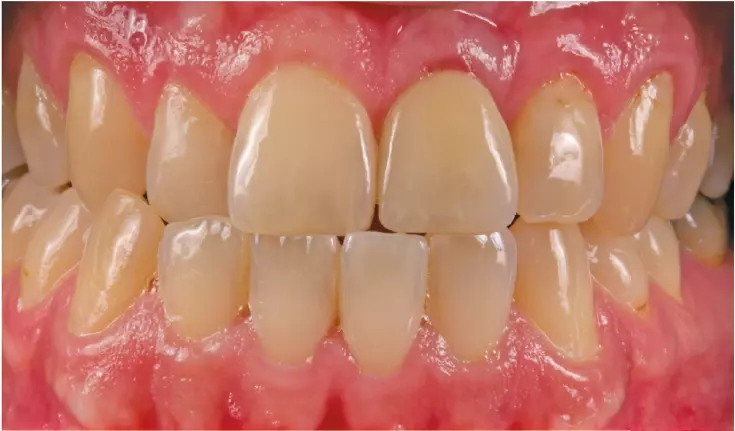

Im Anschluss wurde die Zirkonkrone mit Hilfe von Individualmassen (Creation ZI CT Firma Willi Geller) individualisiert und verblendet (Abb. 25 und 26). Nach Fertigstellung der Krone wurde sie mithilfe von Multilink Implant und Monobond Plus (Ivoclar Vivadent) mit einer Titanbasis für CAD/CAM (Thommen Medical) verklebt. Vom Zahnarzt wurde die provisorische gegen die definitive Krone ausgetauscht (Abb. 27).

Mithilfe dieser Technik war es möglich, den ursprünglichen Wurzeldurchmesser zu erhalten und nicht über eine lange zeitaufwändige Ausformung neu gestalten zu müssen.